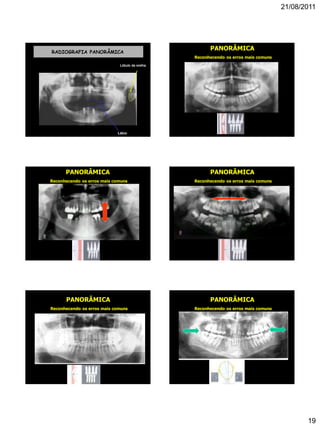

RADIOGRAFIA PANORÂMICA

Lábio

Lóbulo da orelha

PANORÂMICA

Reconhecendo os erros mais comuns